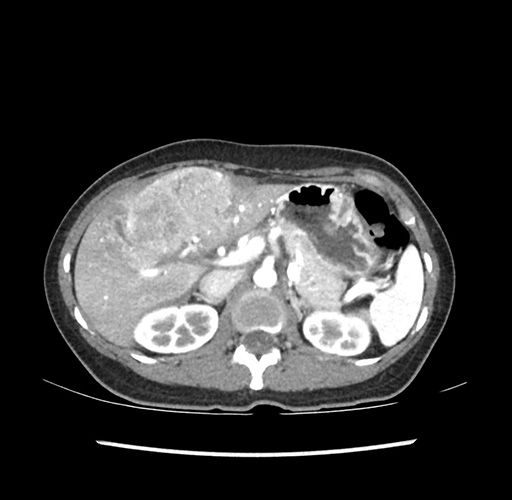

Imaging Analysis

Look through the patient's CT scan to identify any areas of concern for the necessary procedure.

Based on your CT findings, which issue(s) would give reason for "planned slowing down moment(s)" in this case?